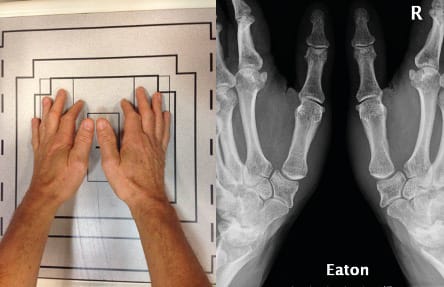

This is also divided into four stages, with normal joint space preserved in the first stage, combined with joint swelling and presumed preservation of joint cartilage. The second stage shows slight joint space narrowing with the joint contour preserved. Bone debris, if present, measures under 2mm. It is assumed that there is moderate joint cartilage degeneration. At stage 3 joint involvement is already very marked. Sclerosis is seen as well as subchondral cystic changes. Osteophytes are larger than 2mm. The triscaphoid joint, however, seems normal. At stage 4, very pronounced joint involvement is seen at both the TMC joint and the triscaphoid joint. This fourth part of the classification was added to the initial classification dating from 1973 [4] Eaton RG, Littler JW. Ligament reconstruction for the painful thumb carpometacarpal joint. J Bone Joint Surg Am 1973;55:1655-66 on Eaton’s second publication in 1984 [5] Eaton RG, Lane LB, Littler JW, Keyser JJ. Ligament reconstruction for the painful thumb carpometacarpal joint: a long-term assessment. J Hand Surg Am 1984; 9A (5), 692-9.

Eaton’s views are the same as Kapandji’s frontal view, except that in the Eaton series the images are comparative (Figure 4), which means that a stress view (Figure 5) is taken so that the joint space can be assessed for any collapse when put under stress.

Radiological assessment of painful basal thumb arthritis will consist of Kapandji’s frontal and lateral views, an Eaton frontal view (which can replace Kapandji’s frontal view if necessary) and stress view of the TMC, a dynamic triscaphoid view and a Gedda's (Bett’s) view [12], Gedda KO (1954). Studies on Bennett’s fracture: anatomy, roentgenology and therapy. Acta Chirurgica Scandinavica, 193(Suppl): 1. [13] Taleisnik J. The Wrist, 1st edn. New York, Churchill Livingstone, 1985: 95–96. (Figure 9).

The value of dynamic views is illustrated very clearly in Fig. 12, showing a Dell stage II, Eaton stage 3, TMA 1, TMI 1, STT 0 joint, which, when seen under stress, suddenly becomes Dell stage II (unchanged) Eaton stage 3 and TMA 3, TMI 1, STT 0 (Figure 13). This demonstrates that Allieu’s classification has greater precision for the TMA [8] Vigouroux F, Rabarin F, Jeudy J, Bigorre N, Saint Cast Y, Pechmajou L, Raimbeau G. Peritrapezial osteoarthritis: Inter – and intraobserver reliability of the Allieu classification. Hand Surg Rehab 36 (2017) 363-367 .